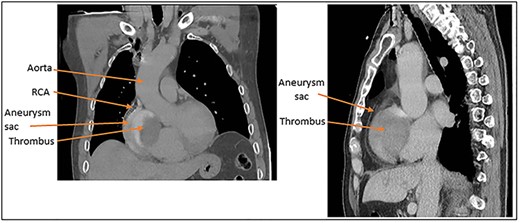

(A) Coronal and (B) sagittal CT images of the large aneurysm sitting over the right side of the heart and the thrombus within the aneurysm.

The patient then underwent a CT to better visualise the aneurysm, shown in Fig. 2. The RCA was seen to be feeding a localised, well circumscribed, lesion with layering of material suggestive of acute bleeding from the RCA into a possible pre-existing aneurysm.